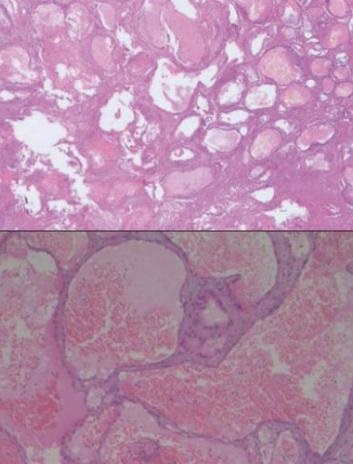

Prin ea insasi, tumora creste lent și nu formează metastaze. Caracteristica principală de localizare - cavitatea corpului vertebral, precum și substanța cartilaginoasă între ele. Cu toate acestea, există alte locuri, mai rare și neobișnuite în oase. În materie de maduva spinarii sunt, de asemenea, de multe ori identificat divizarea celulelor de date vasculare patologice, care confirmă originea locală a educației în creștere.

Dintre toate tumorile osoase ale corpului hemangiomul coloanei vertebrale este nevoie de formațiuni patologice a zecea reprezentate aici prin curgeri ambele simptome clinice turbulente si de a fi constatare aleatoare la examenul histologic.

Pe vertebra deja modificate după naștere de-a lungul vieții lor va oferi o varietate de efecte mecanice și fizice care pot contribui la apariția microtrauma constantă și hemoragie a vaselor de sânge subțiri și fragile morfopatologic. Pentru a opri reacțiile de coagulare activat hemoragie organism, inclusiv formarea unei cantități masive de cheaguri de sânge la nivel local. La celulele același timp activate, osteoclastelor, care distrug osul grinzi corpurile vertebrale și promovarea creșterii de noi vase pe locul gol după procesul de recanalizarea de cheaguri de fibrină de sânge. Deci, încet, dar sigur, există o creștere a conglomerat vasculare patologice.